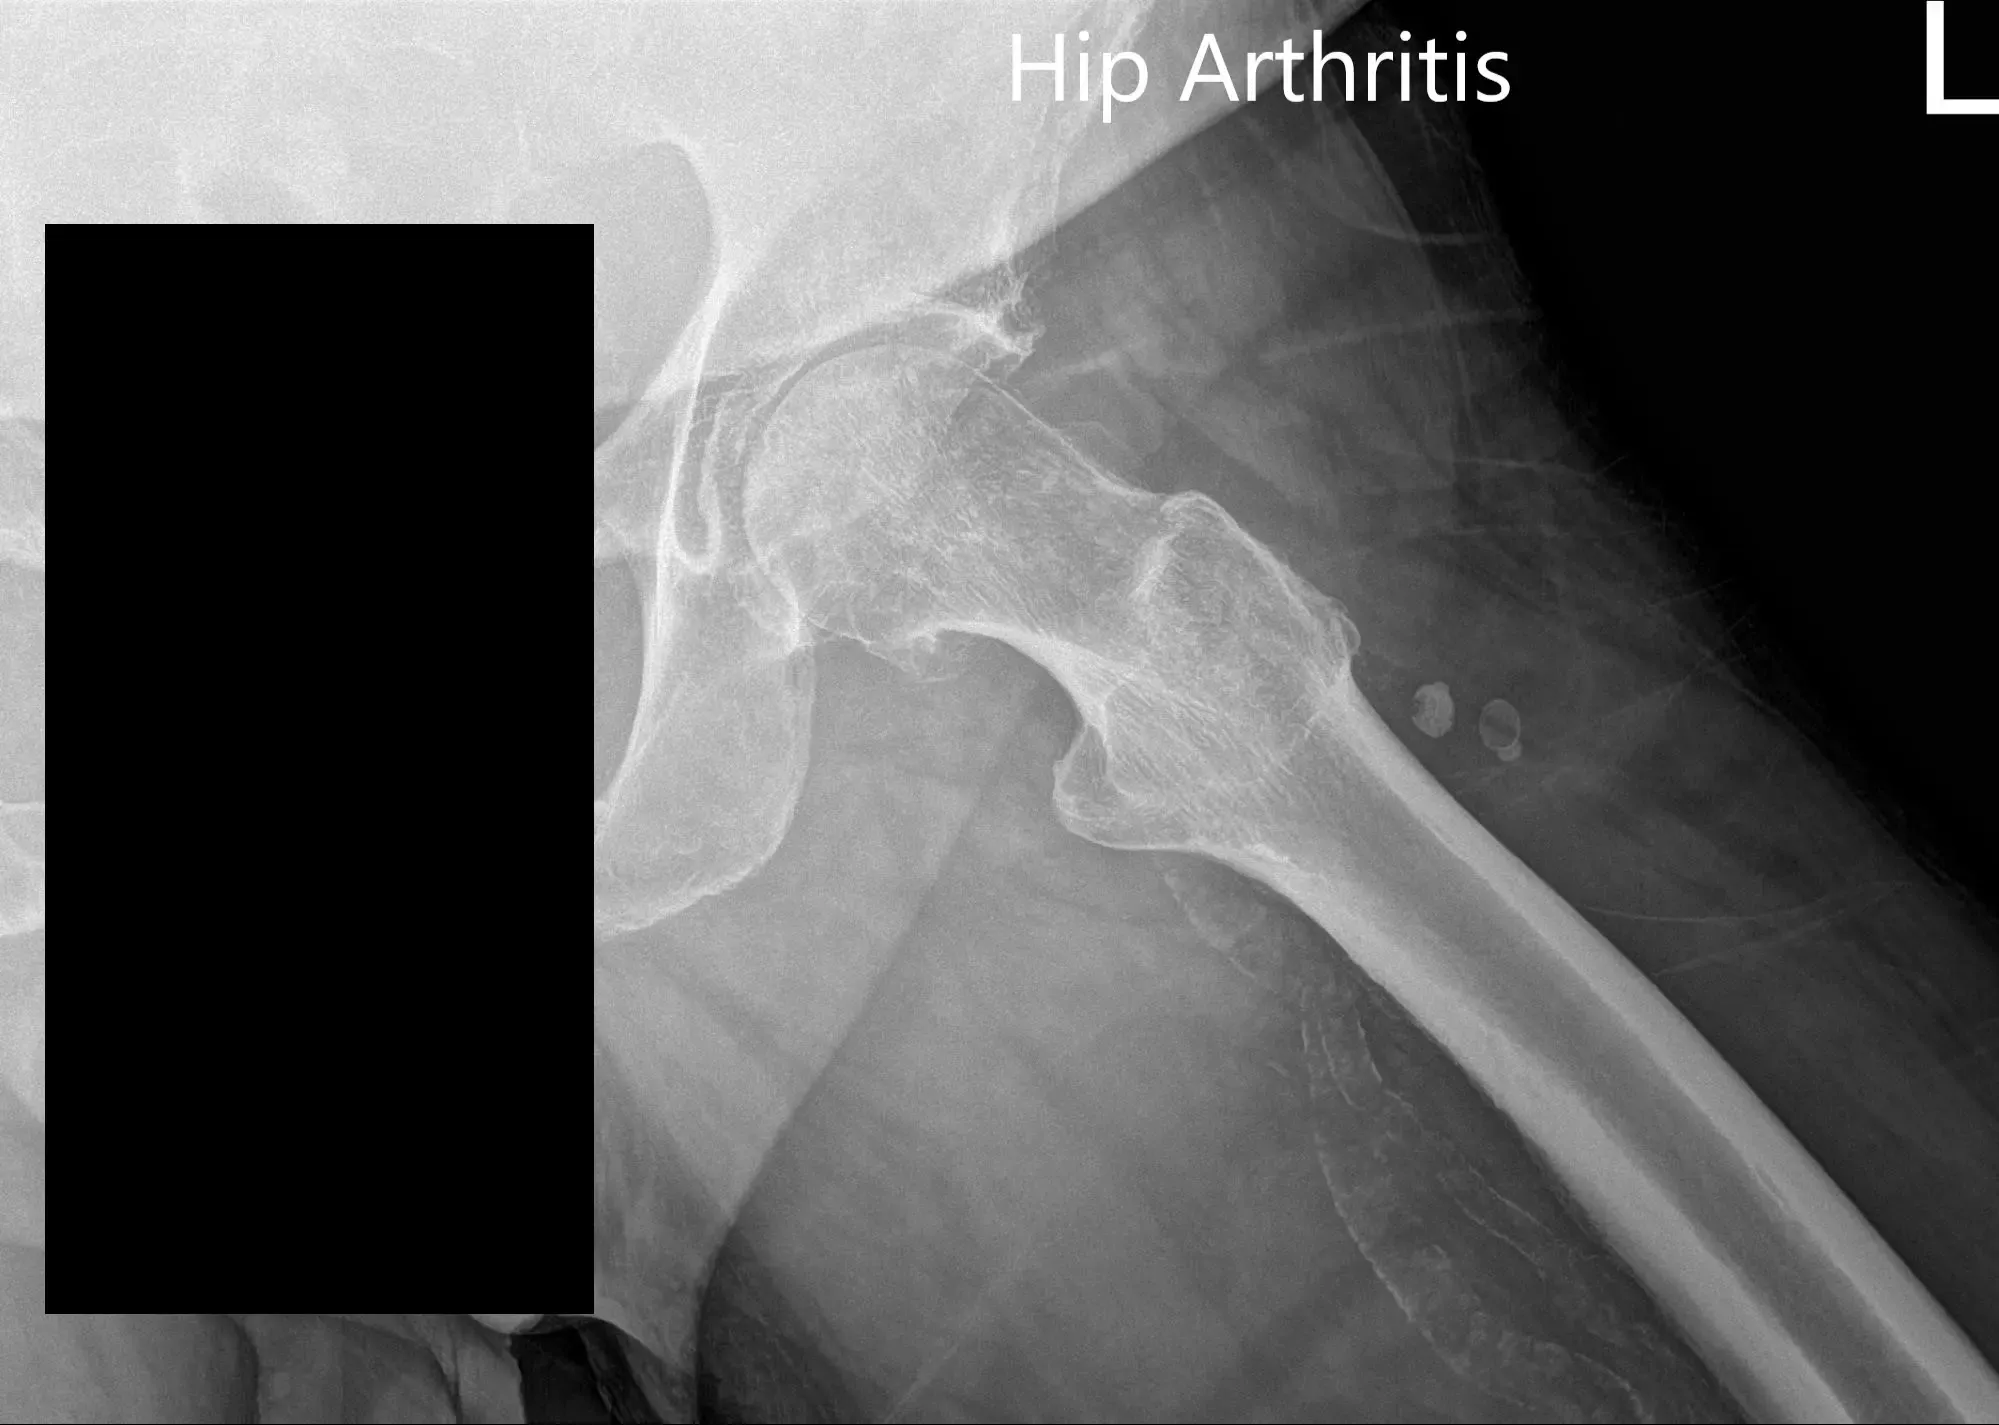

Las imágenes revelaron una osteoartritis severa en la cadera izquierda. Teniendo en cuenta las condiciones médicas de los pacientes y el dolor de cadera que limitan el estilo de vida, se le recomendó una prótesis total de cadera para la izquierda. Se discutieron extensamente los riesgos, beneficios y alternativas. Ella aceptó seguir adelante con el procedimiento.

Radiografía preoperatoria de la cadera izquierda que muestra visión AP y vista lateral con patas de rana